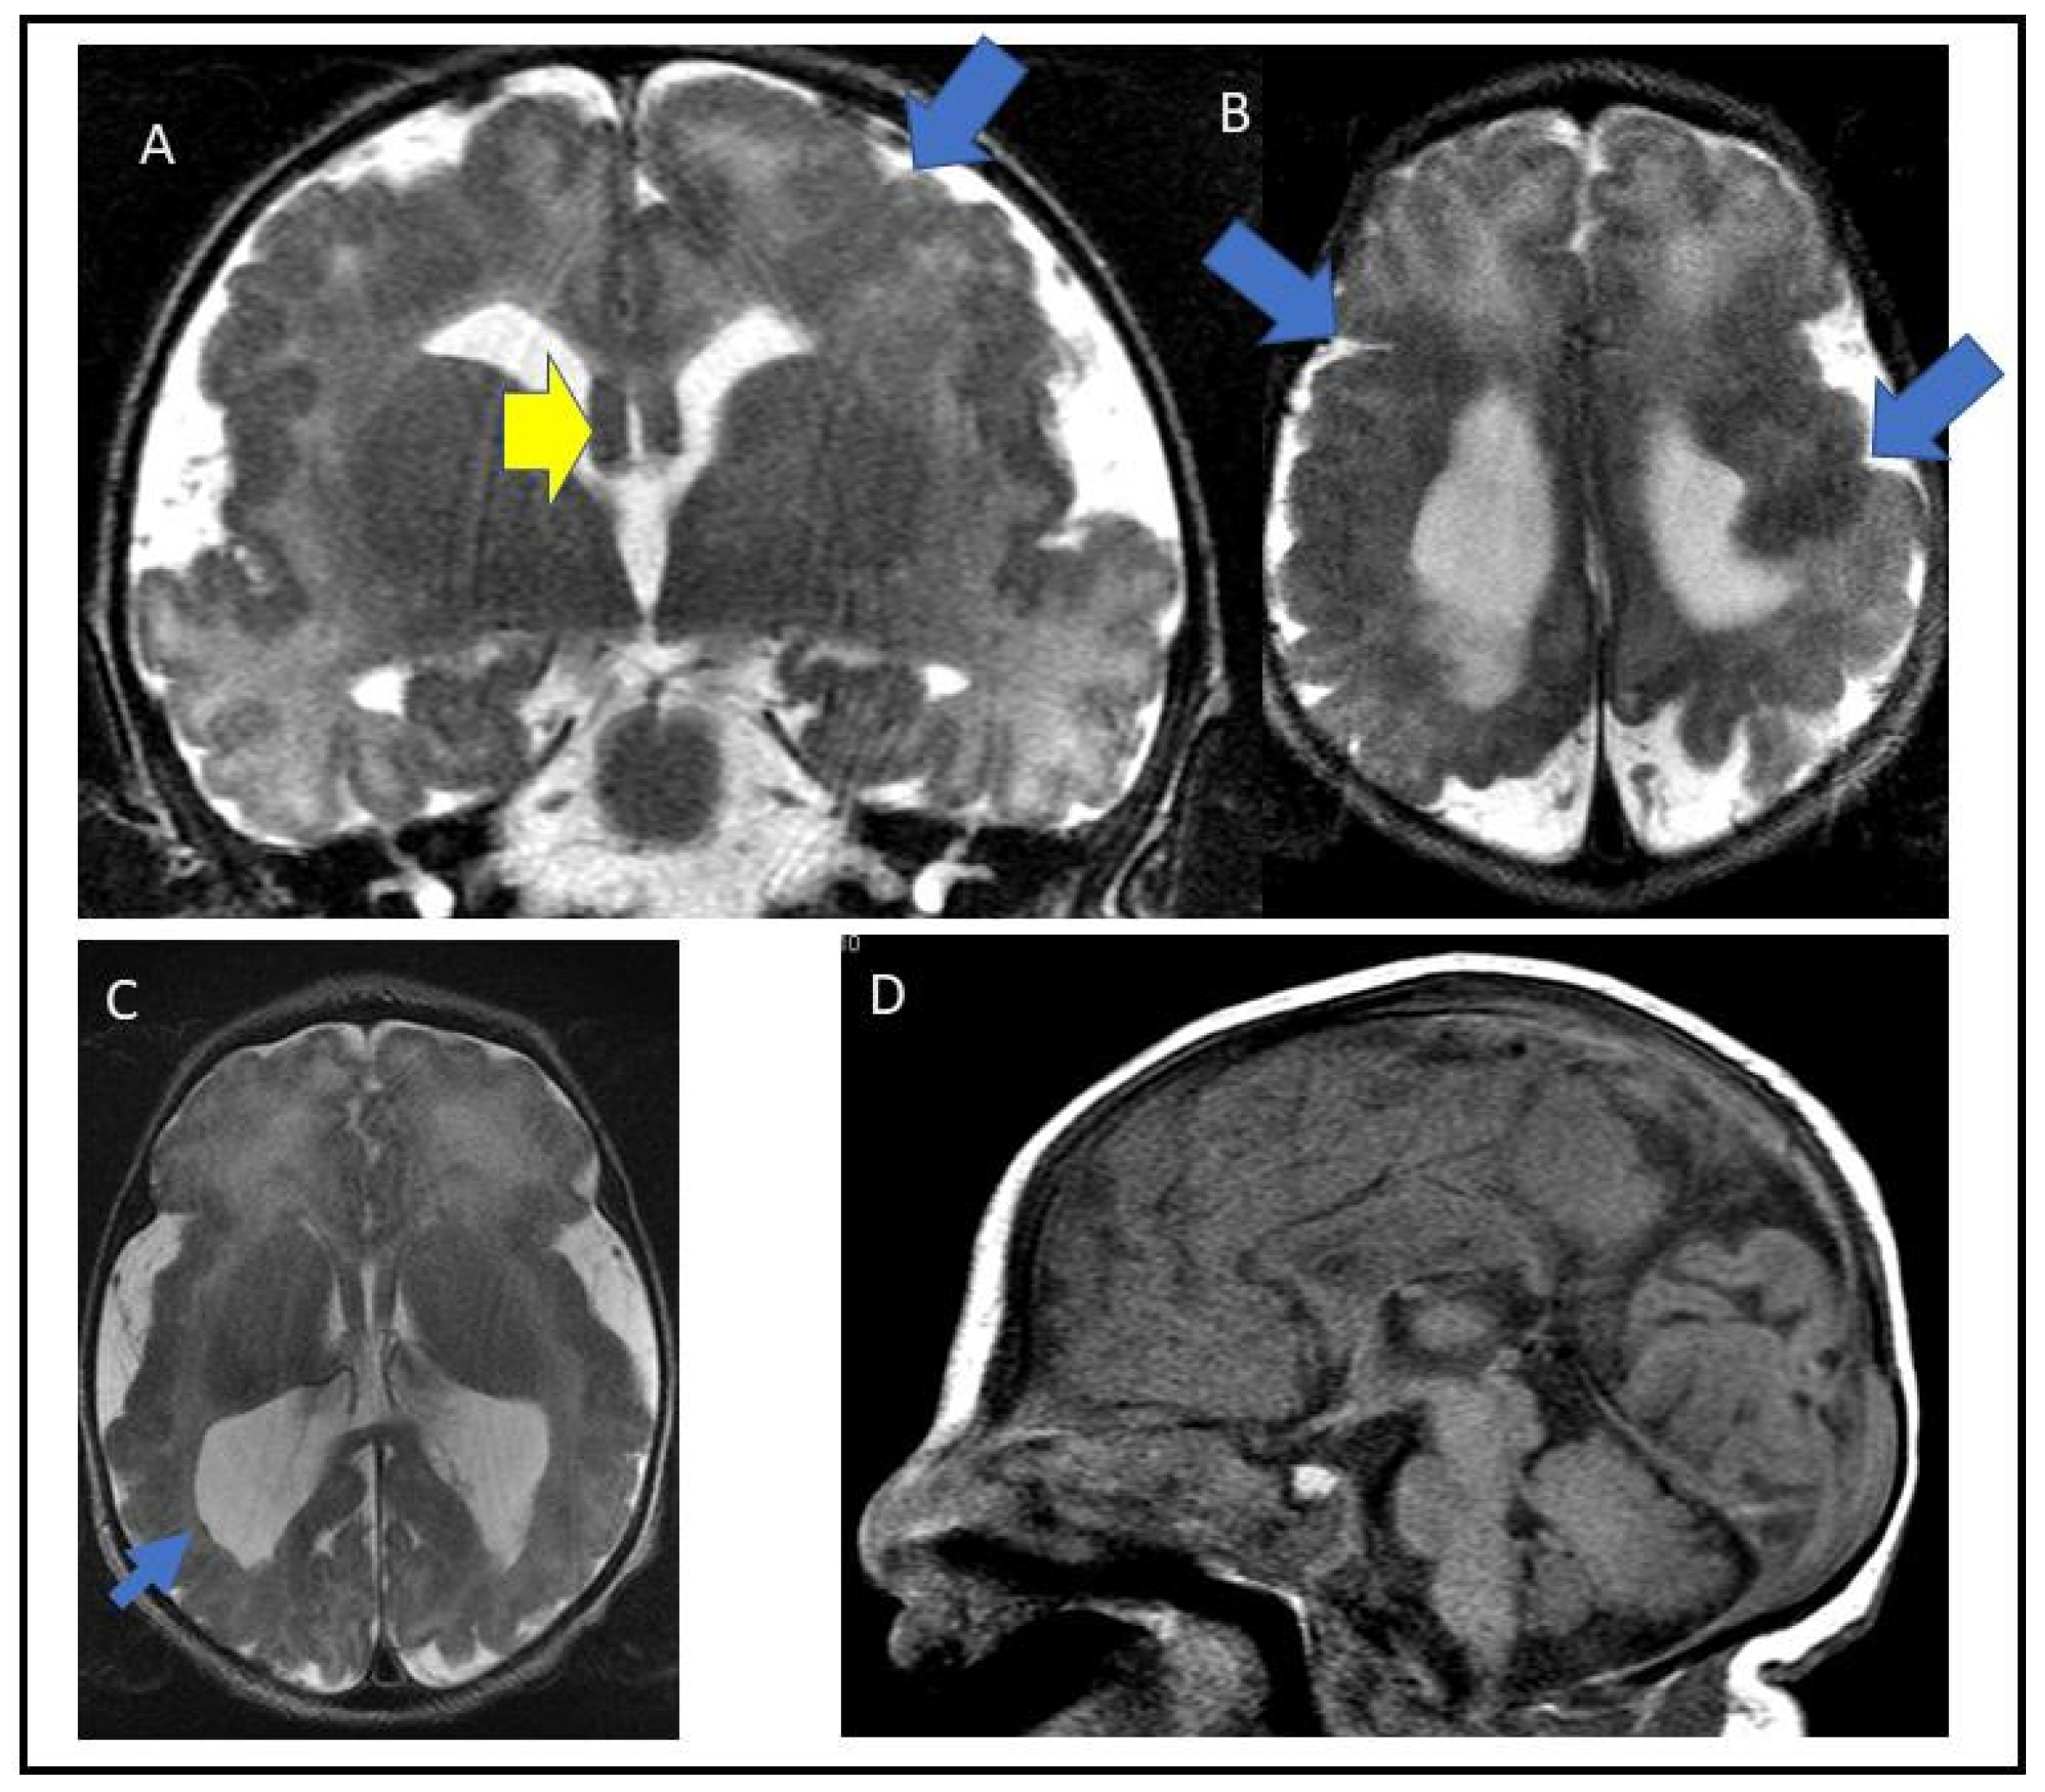

A De Novo Missense Variant in TUBG2 in a Child with Global Developmental Delay, Microcephaly, Refractory Epilepsy and Perisylvian Polymicrogyria

3.1. Case Report